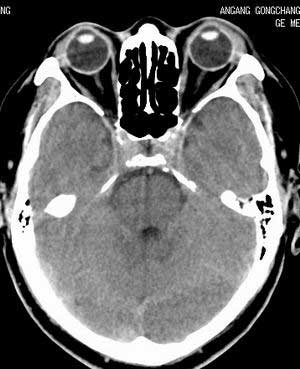

正常平扫片,右侧为血管影。

横窦乙状窦。

增强的横窦乙状窦。